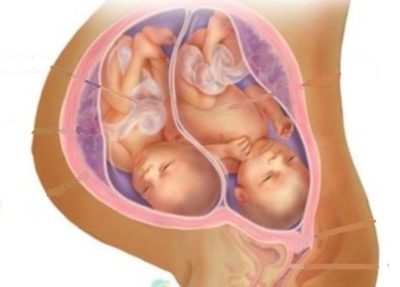

குழந்தை தலை கீழே இருக்காமல் குதம் கீழே இருக்கும் தன்மை (breech), கால்கள் கீழே இருக்கும் தன்மை (footling), இரண்டு குழந்தைகள்(twins), குழந்தையின் தலையும் தாயின் இடுப்பெலும்பும் ஒத்துப்போகாத தன்மை (cephalo pelvic disproportion), நஞ்சுக்கொடி கீழிறங்கி இருக்கும் தன்மை (placenta previa), நஞ்சுக்கொடி கழன்று கீழிறங்கி தொங்குதல்(abruptio placentae) இப்படி கர்ப்ப காலத்தில் குழந்தை மற்றும் நஞ்சுக்கொடி எப்படி இருக்கிறது என்பதெல்லாம் மருத்துவச்சிக்கு தெரியாது.

ஆகவே குதம் கீழே இறங்கிய நிலையில் உள்ள குழந்தையாக இருந்தாலும் சரி,

இரட்டையர்களாக இருந்தாலும் சரி, தலையும் இடுப்பெலும்பும் ஒத்துப்போகாத தன்மை இருந்தாலும் சரி, தாய்க்கு வலி வந்தவுடன் மருத்துவச்சி பிரசவம் பார்க்க ஆரம்பிப்பார்.